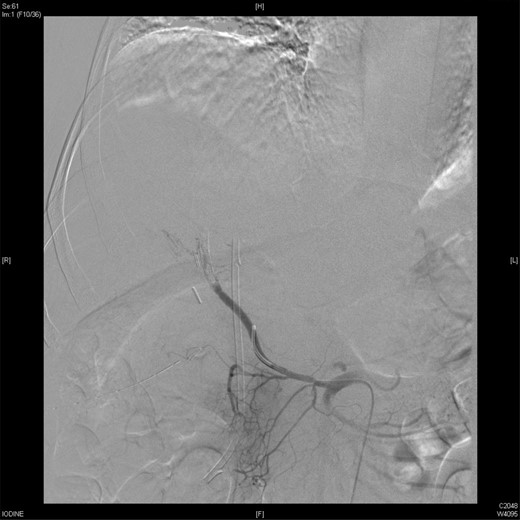

Upon presentation to our center, the patient was febrile (38.9°C) and complained of a left upper limb pain and swelling. The surgical drain was draining a mixture of bile and blood. His WBC count was 14 × 109/l, total bilirubin 35 µmol/l and the direct bilirubin 21 µmol/l. A duplex ultrasound of the upper limb revealed a left brachial vein thrombosis. Hematology was consulted, and a diagnosis of acute upper limb venous thrombosis was established. Owing to the presence of blood in the drain, he was kept on the maximum prophylactic dose of unfractionated heparin. A CT angiography of the abdomen showed two collections, one at the surgical bed near the drain, and the other was subcapsular below the left lateral lobe of the liver, as well as an aneurysm of the replaced right hepatic artery with an active bleeding blush (Fig. 1). The patient was immediately referred for an angiography, which confirmed the CT scan findings (Fig. 2). An arterial stent was inserted at the location of the aneurysm (Fig. 3), and a pigtail drain was inserted to drain any residual collection. An ERCP was also performed, which revealed a Strasberg Class D injury, and a plastic biliary stent was inserted. After the angio-stent insertion and stabilization of the patient, heparin infusion was started. Five days later he developed hematemesis and melena with a significant drop in his Hb to 2 g/l, and his total bilirubin became 183 μmol/l of which 91 μmol/l is direct. A gastroscopy was performed and showed hemobilia (bleeding from the ampulla of Vater). Subsequent angiography demonstrated a leak of contrast just above the arterial stent; hence, a further stent was placed to cover that area of the aneurysm. Similar symptoms reoccurred a week later, and a new angiography showed a new aneurysm from the left proper hepatic artery. A percutaneous thrombin injection of the aneurysm was performed as the bleeding branch was unreached via direct angiography and was filling in retrograde perfusion. During recovery a chest spiral CT was performed, which revealed the diagnosis of a bilateral segmental pulmonary embolism. Heparin infusion with low targets of partial thromboplastin time of 50–60 was started.

An angiographic scan showed superior mesenteric artery (straight arrow) and replaced right HAP (angulated arrow).